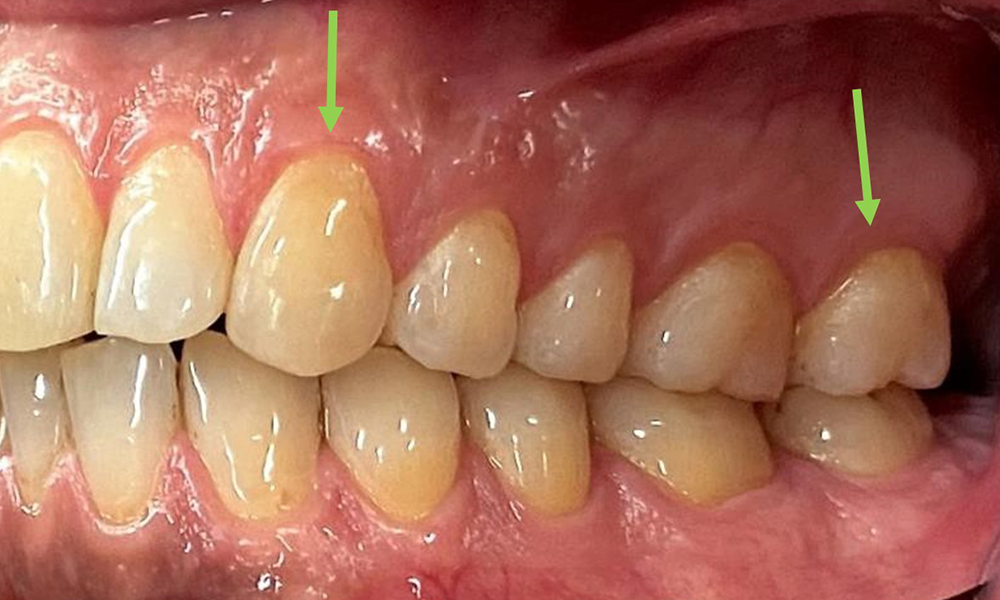

The patient has full dentition with a total of 28 teeth. There were noteworthy erosions and attritions. (Fig. 4, Fig. 5). Due to bruxism, the patient has been wearing a splint with an adjusted bite block at night for many years. The erosions were caused by long-term consumption of isotonic beverages. No periodontal bone loss or active caries were observed.

Close-up view of teeth

Fig. 5: Close-up view of teeth 45 to 47. The green arrows show dental attrition and erosions of the buccal cusps with partial enamel loss, © Dr R. Krapf